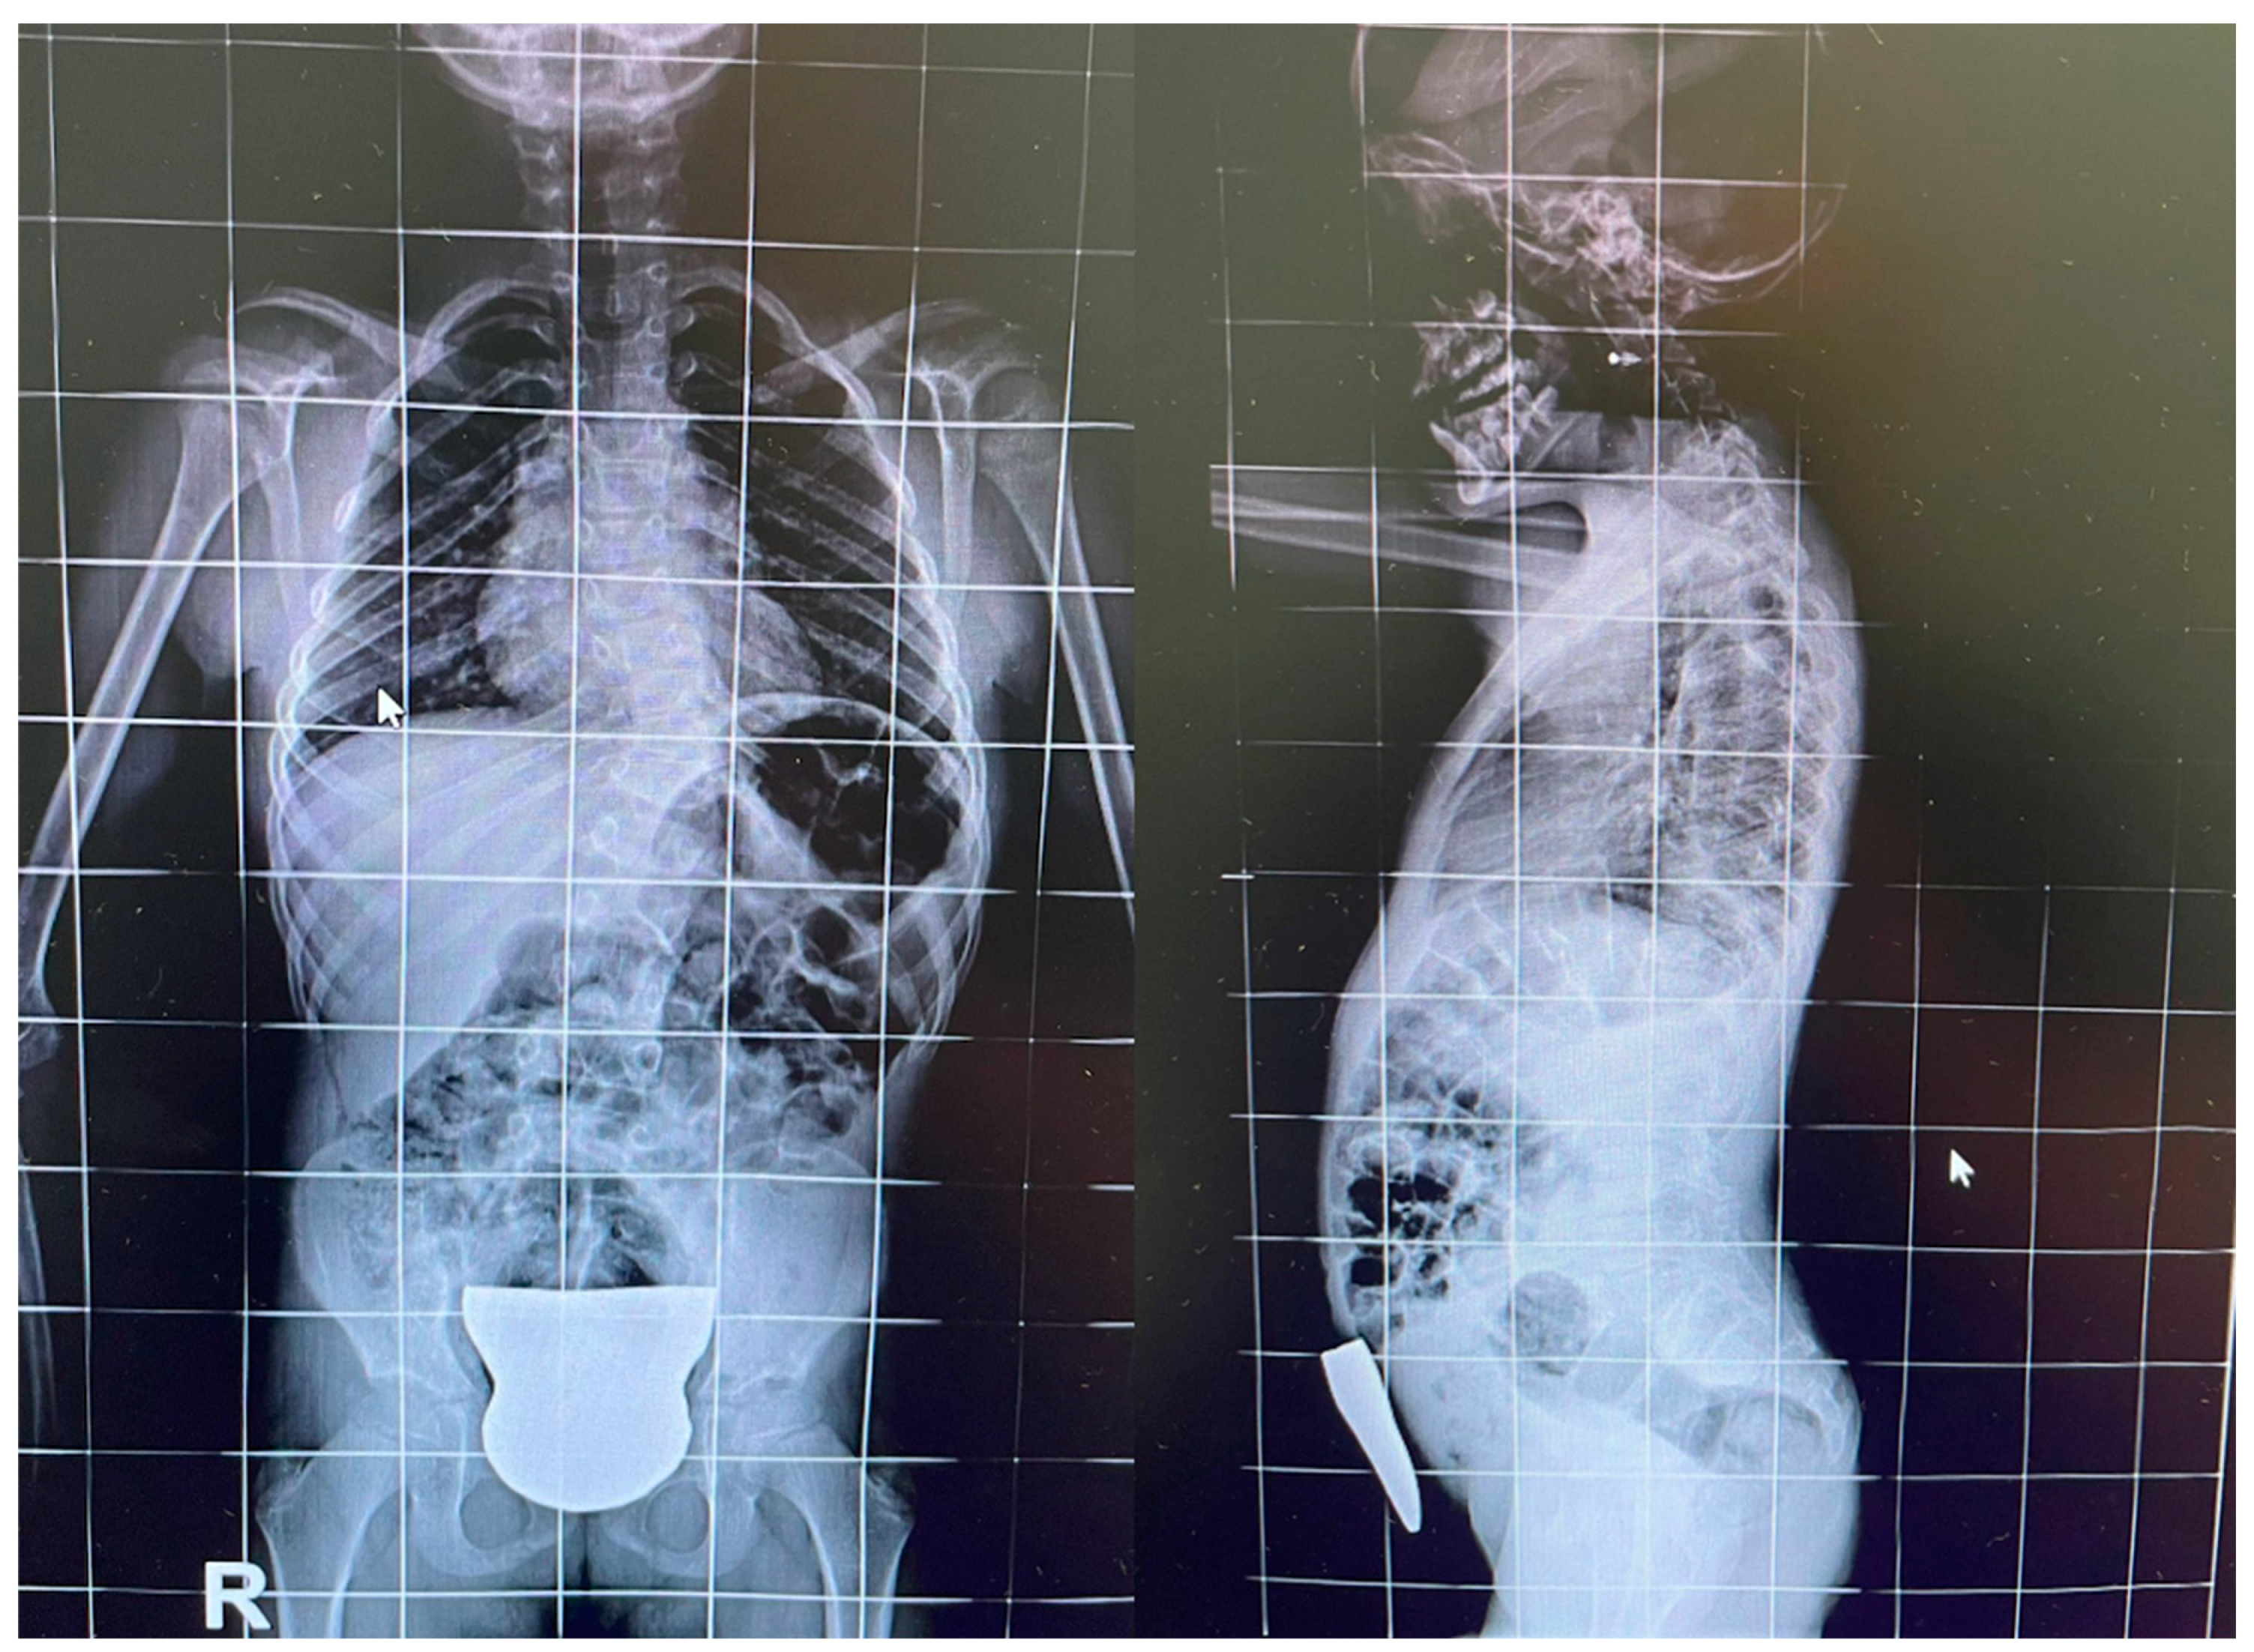

The Synergistic Effects of Incobotulinum Toxin and Physiotherapy in a Rare Case of Paraparesis in a 7-Year-Old Affected by Klippel–Feil Syndrome Related to an MYH3 Gene Mutation: A Case Report

2. Case Report